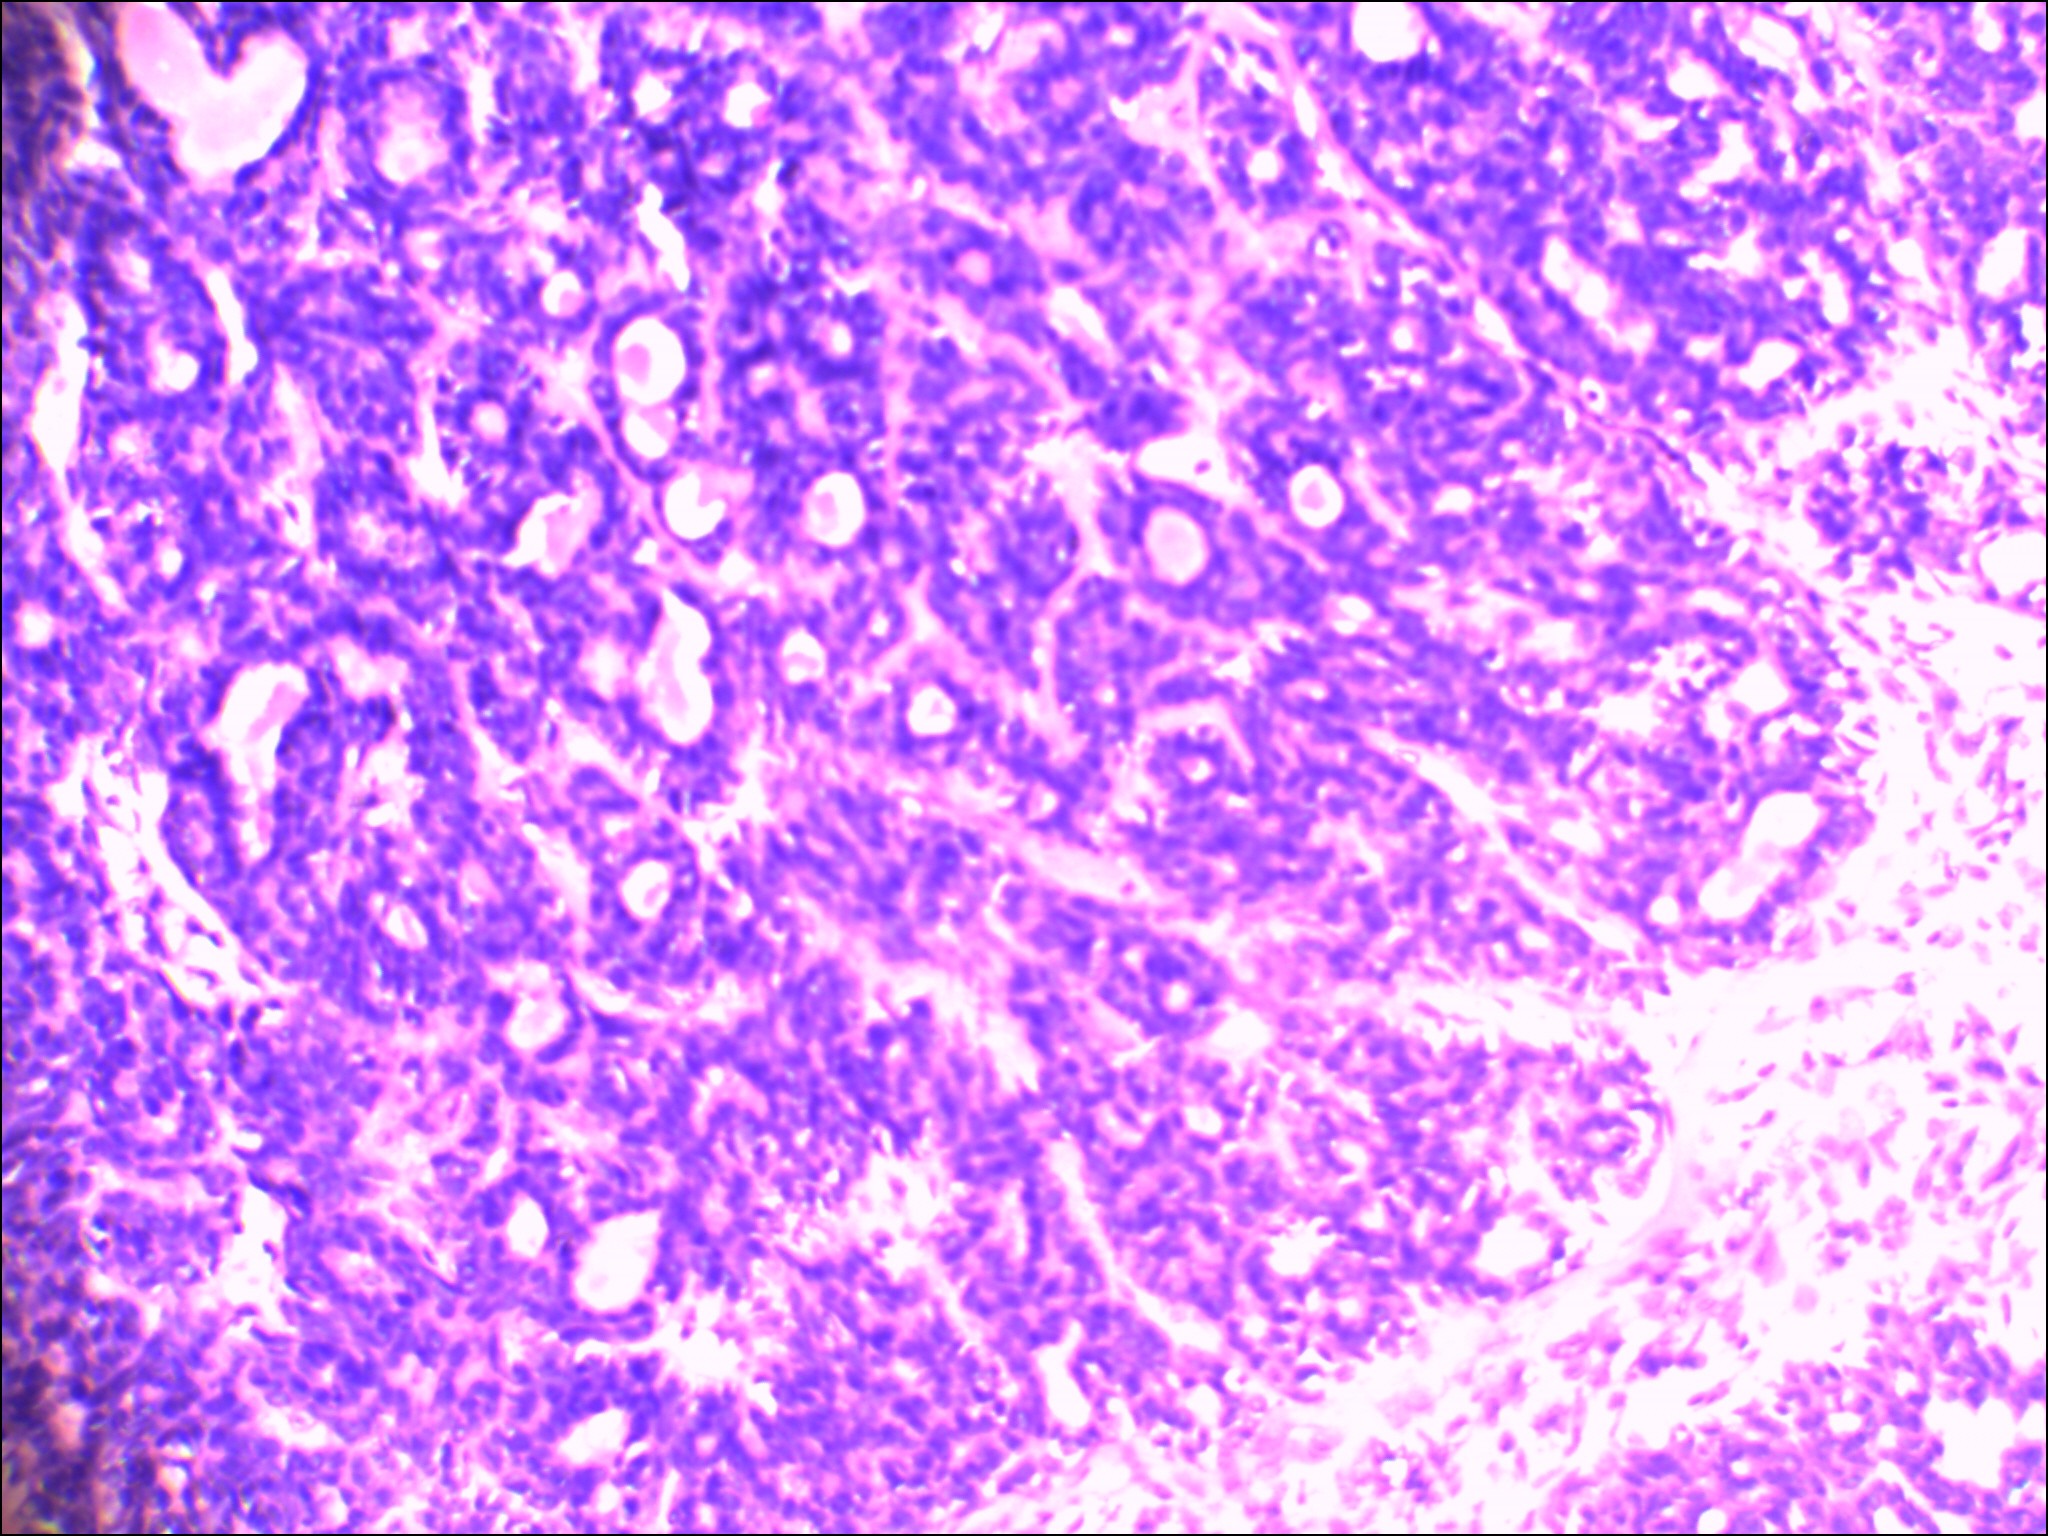

左侧腮腺肿物

性别

女

年龄

48岁

发现颈部肿块20余年

肿块大小:4×3×2.8cm,表面光滑,有包膜,切面灰白色,质硬。

图4

首先考虑基底细胞腺瘤。